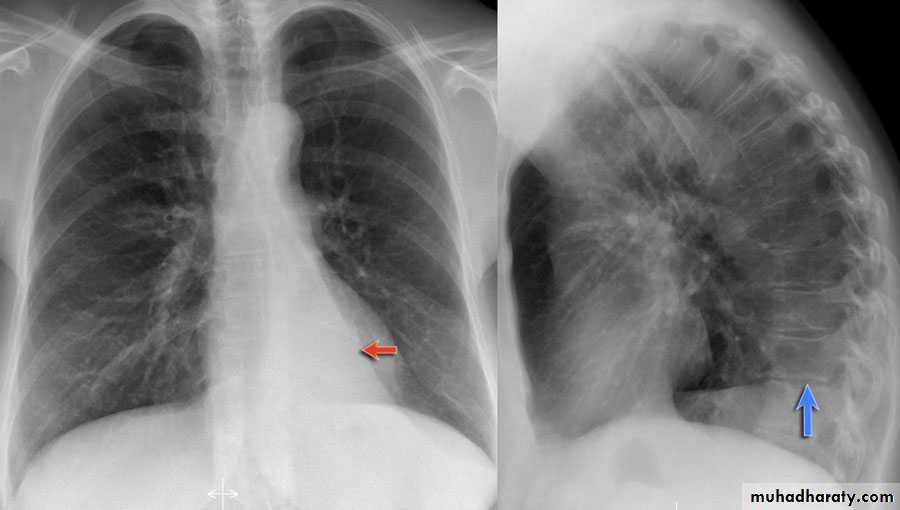

History: dyspnea, weight loss, dehydration with poor immunity

History; too shy to take of his shirt in the pool!

What is the difference?